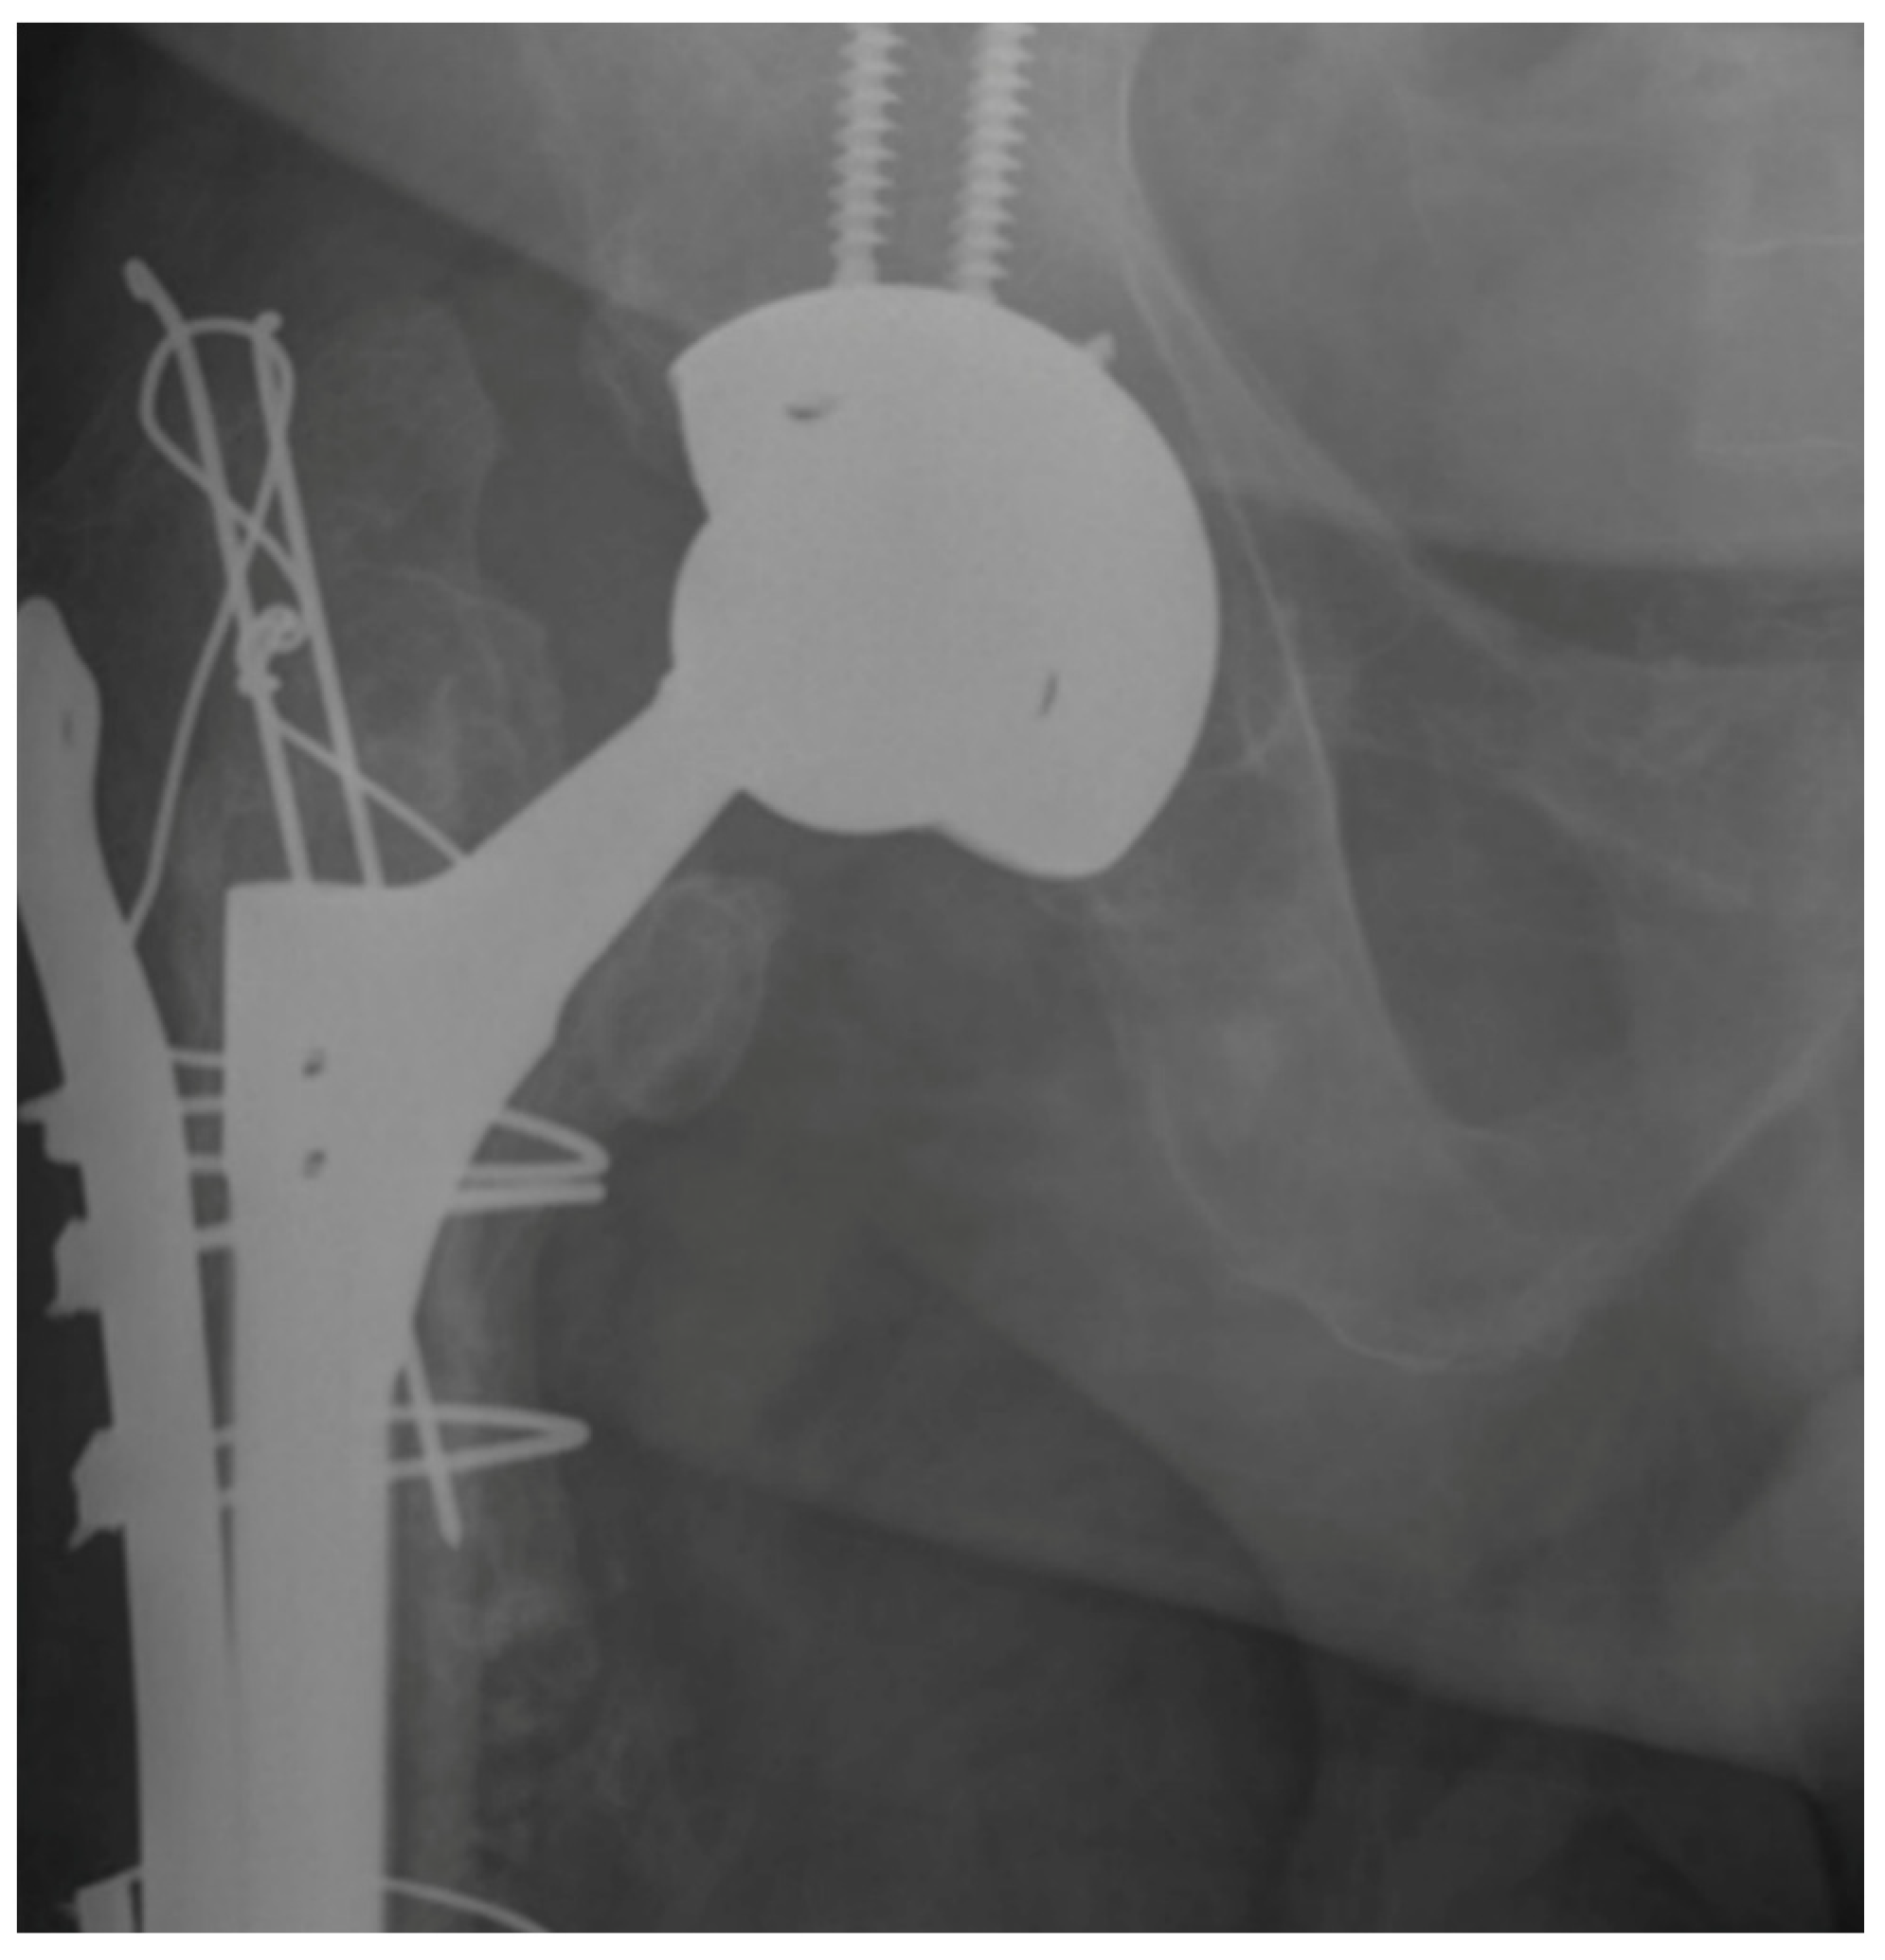

Comparison of Cylindrical and Tapered Stem Designs for Femoral Revision Hip Arthroplasty